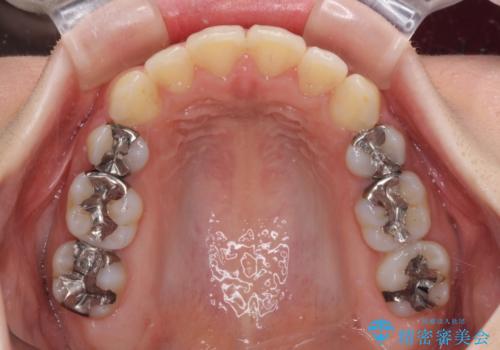

- 上下の出っ歯を気にして来院された患者様です。

口元を積極的に引っ込めるために、上下左右の第一小臼歯を4本抜歯することとしました。

元々ディープバイトのため、スペースを閉じている期間に上下前歯が接触してしまい、治療期間が想定よりも伸びてしまいました。